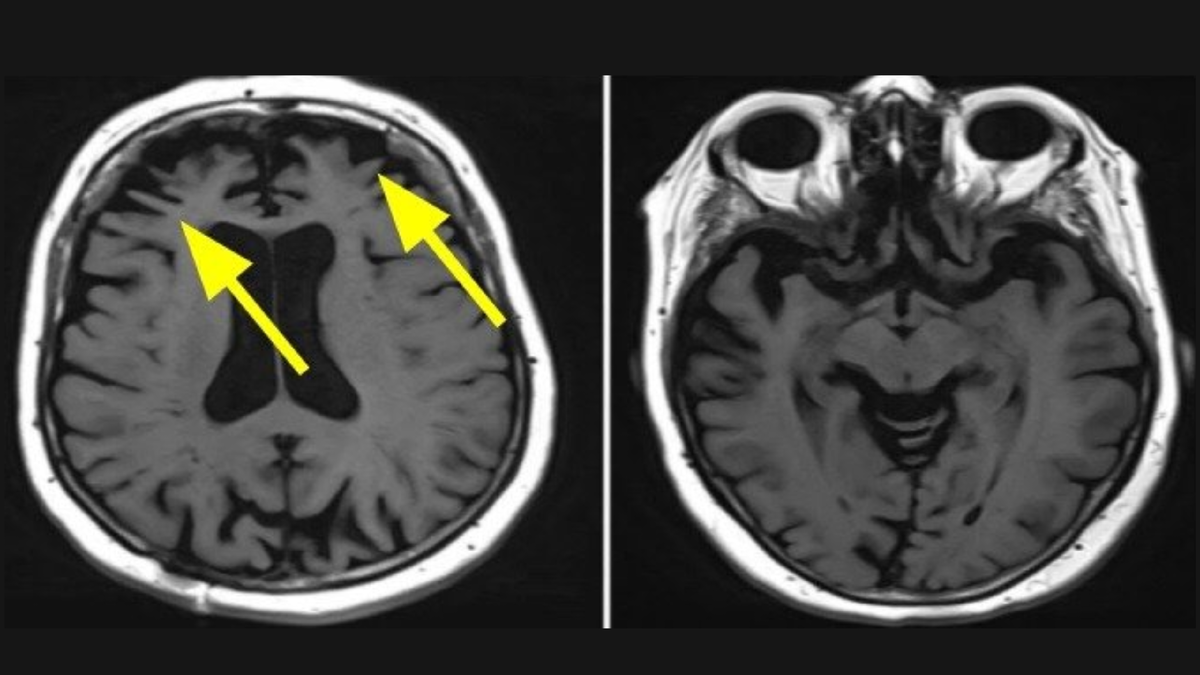

Атрофия вещества головного мозга в лобных областях, истончение извилин. Источник: https://sdelatmrt.spb.ru/

По результатам анализа томограмм было установлено - долгий сон напрямую связан с атрофией вещества мозга в задних отделах, а короткий - с потерей белого вещества в мозжечке и таламусе.